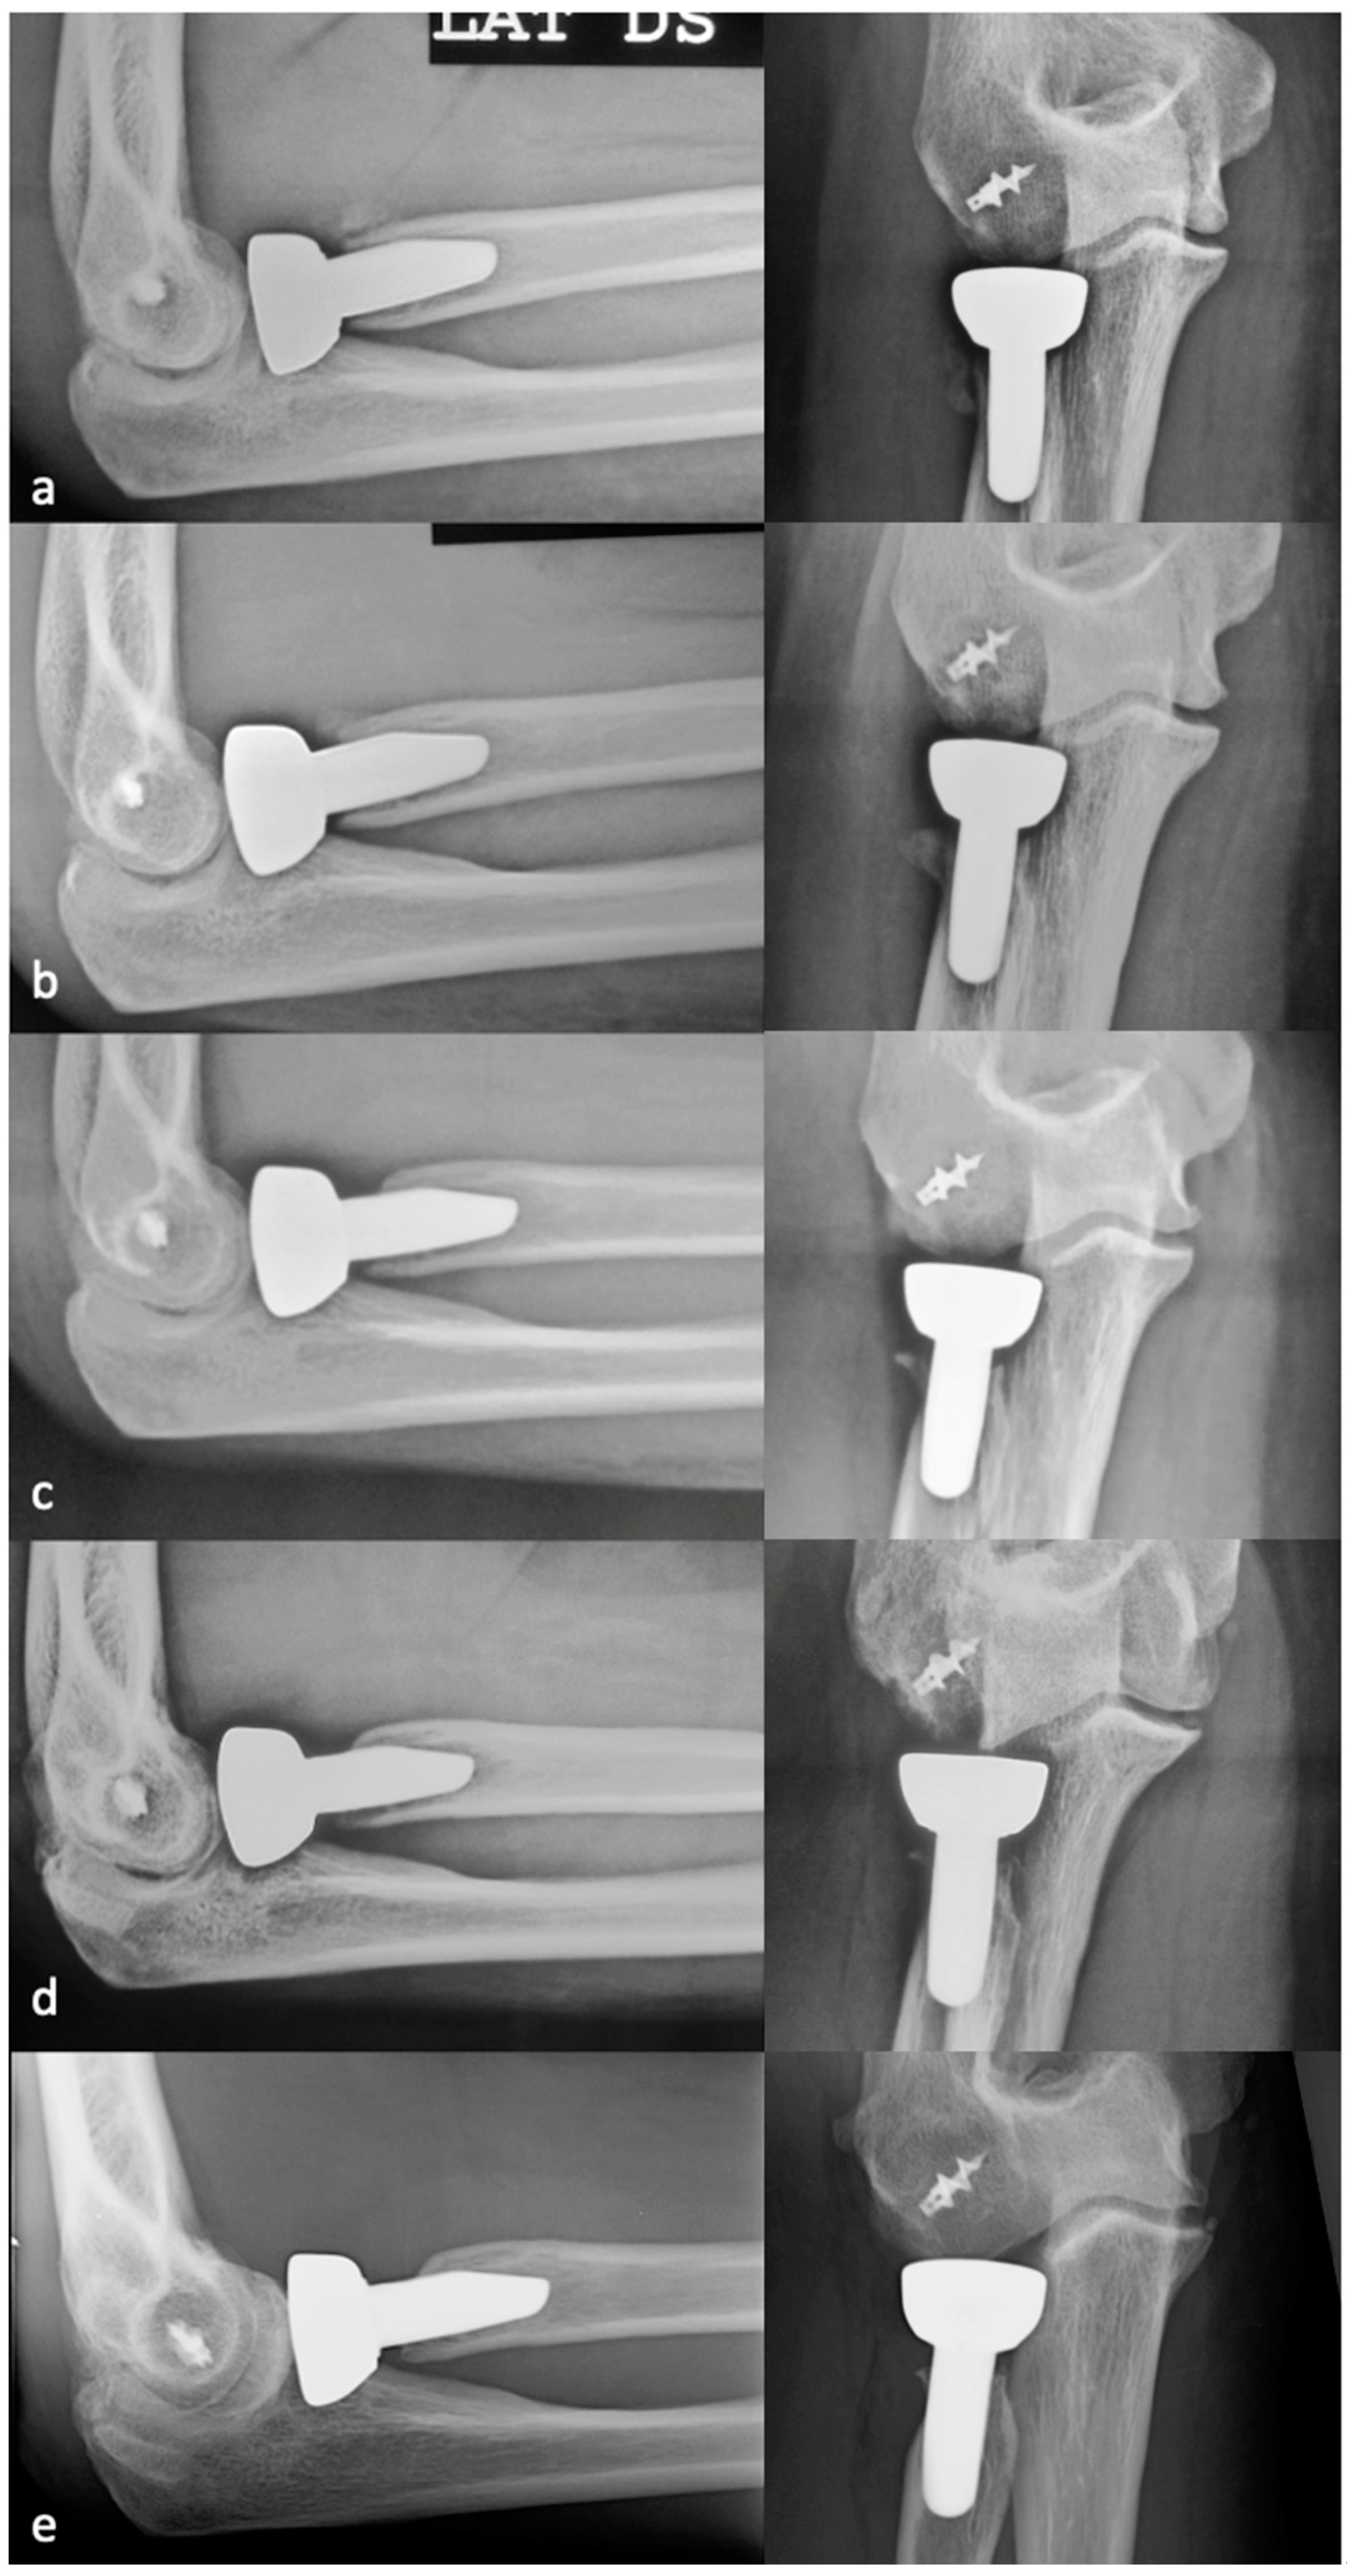

PRNR was mild in 27 patients (33%), who had an mPRNR of 1.9 mm (range: 0–2.9); PRNR was moderate in 44 patients (54%), who had an mPRNR of 4.5 mm (range: 3.1–5.9); lastly, PRNR was severe in 11 patients (13%), who had an mPRNR of 7 mm (range: 6–9.4). The typical progression of PRNR over time for an anatomical RHA is shown in Figure 3, while that for a bipolar implant is shown in Figure 4. Table 1 shows the clinical result scores in the subgroups stratified according to PRNR severity. No significant differences were observed in either the clinical characteristics or the clinical scores between the three subgroups. Indeed, no significant correlations (p = 1) (Table 2) were detected between the degree of PRNR and any of the clinical parameters in each subgroup.

Figure 3.

Progression of PRNR over time in an anatomical press-fit RHA. X-rays performed postoperatively at 2 weeks (a), 6 months (b), 1 year (c), 2 years (d), and 7 years (e). PRNR progressed until the end of the second year, while no further progression was observed beyond 2 years.